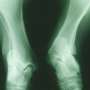

![]() | PPI use ups risk of osteoporosis, osteopenia in femur(HealthDay)—Proton pump inhibitor (PPI) use is associated with increased risk of developing osteoporosis and osteopenia in femur bones, according to a study published online May 31 in the International Journal of Rheumatic Diseases. |